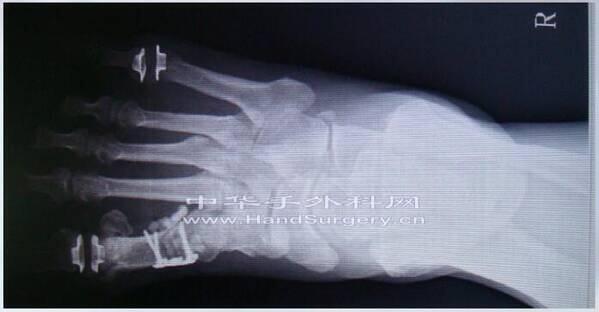

参考云南昆明市第一人民医院张云峰教授课件

小关节Swanson关节置换术注意事项

金属垫片为钛合金材质

可以进行核磁共振检查